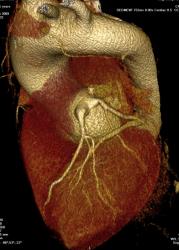

Мы недавно начали проводить КТ-коронарографию. Представляю вариант нормальных сосудов сердца. Довольно типичный вид, тип кровоснабжения преимущественно правый.  Ствол левой коронарной артерии делится на ветви: переднюю нисходящую и огибающую.

Стрелки: Красные - правая коронарная артерия, зеленые - передняя нисходящая, голубые - огибающая артерия, черные - ветвь острого края, желтые стрелки - задняя нисходящая артерия.